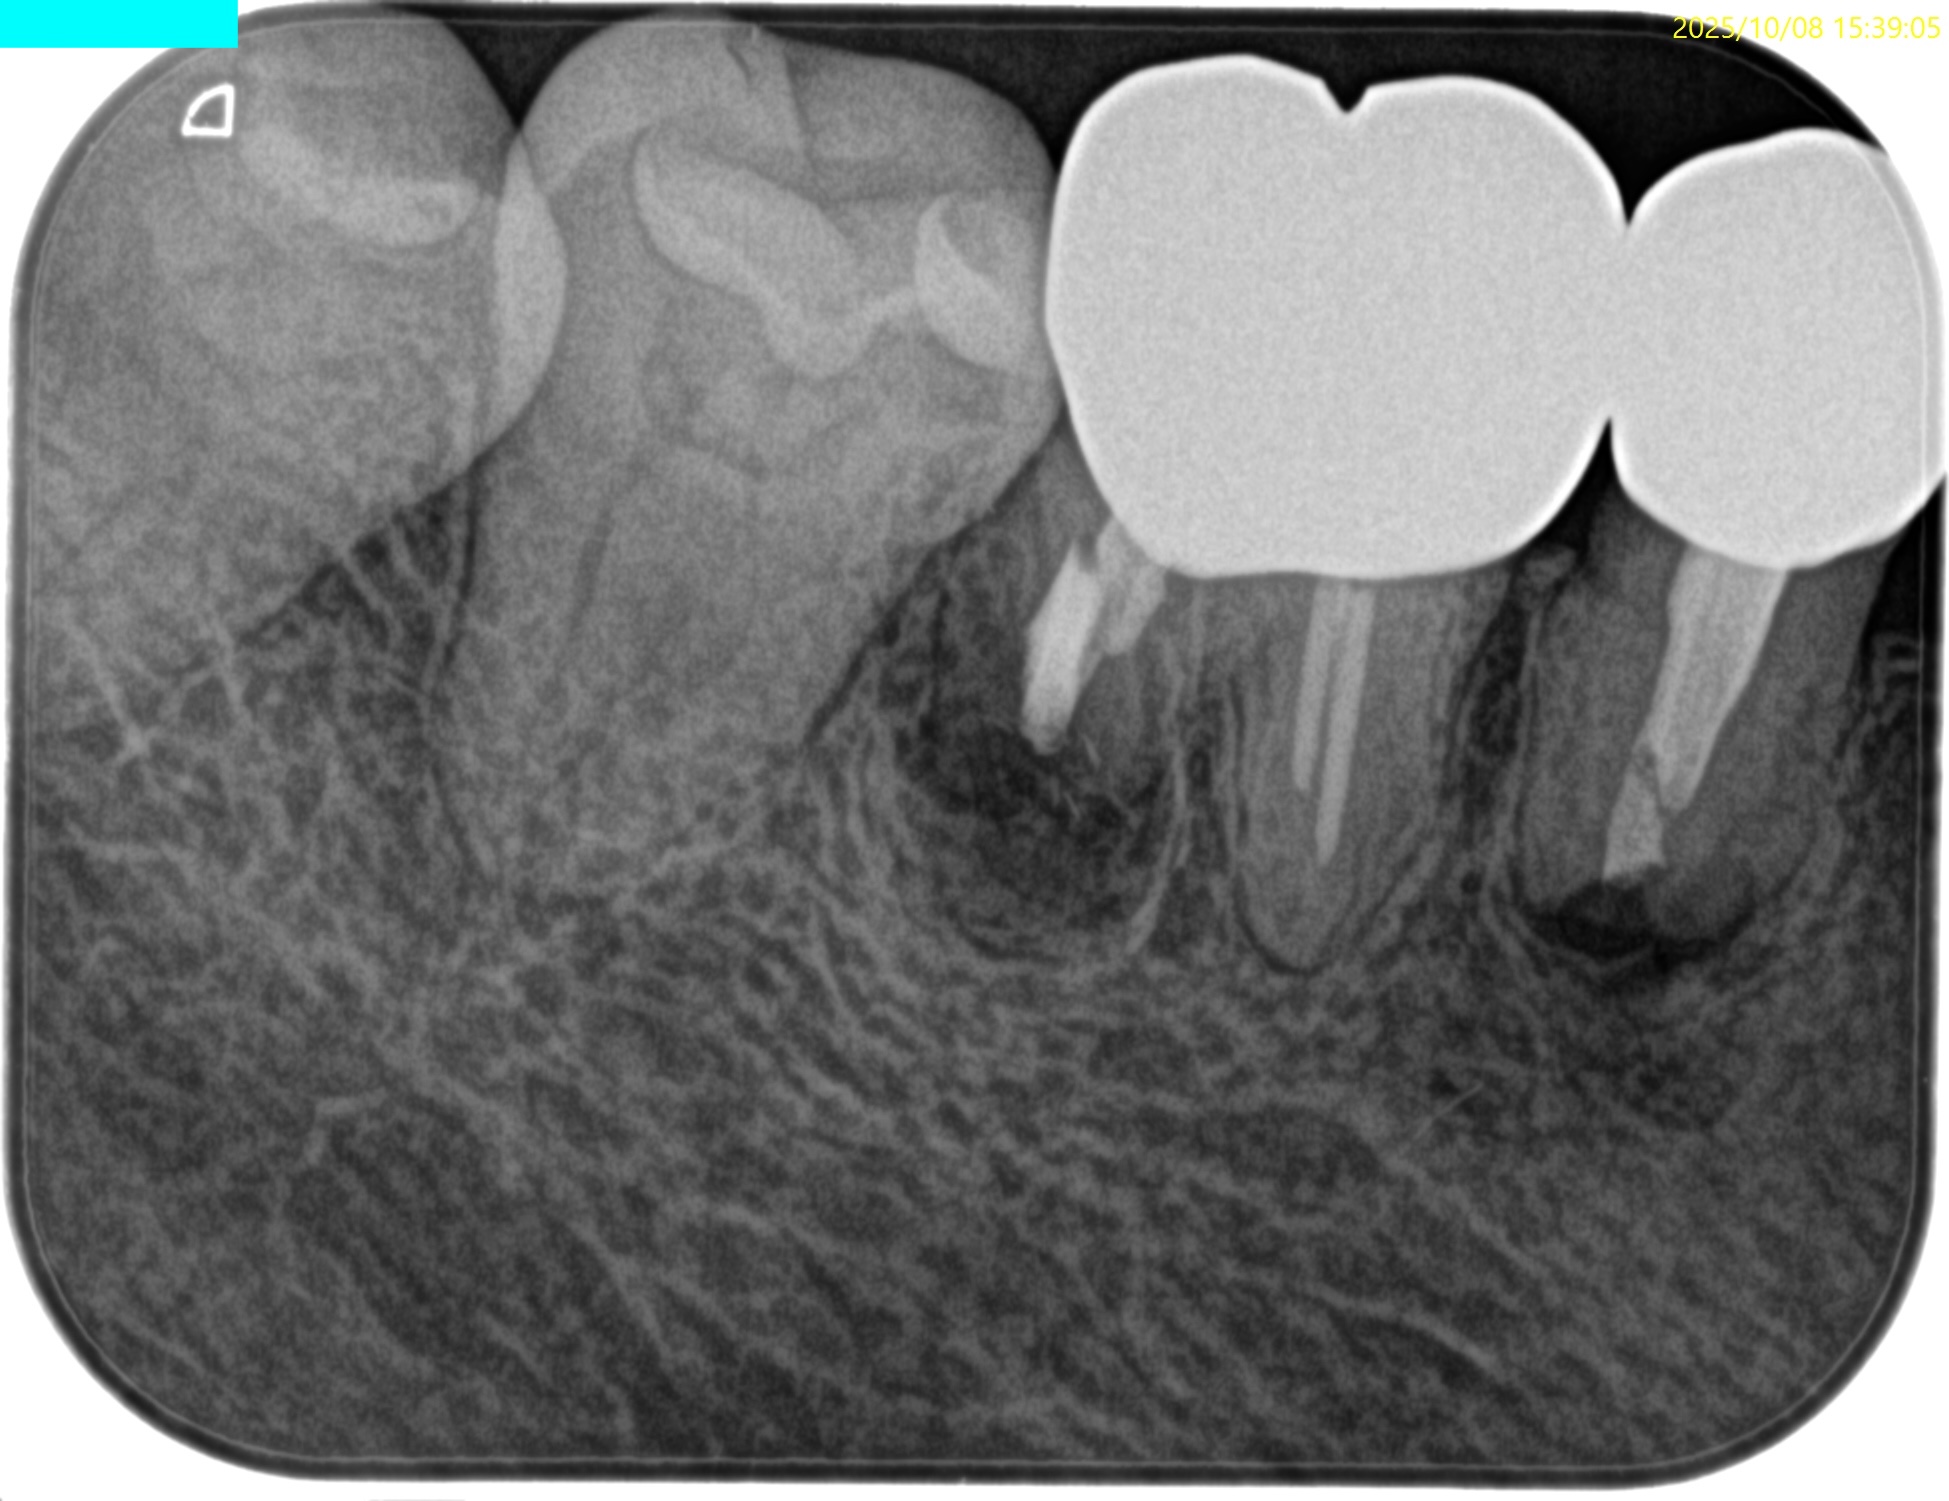

#30 D Apicoectomy(2025.10.8)

私にはD根が歯槽骨から透けて見える。

PA, CBCTを撮影した。

問題はないだろう。